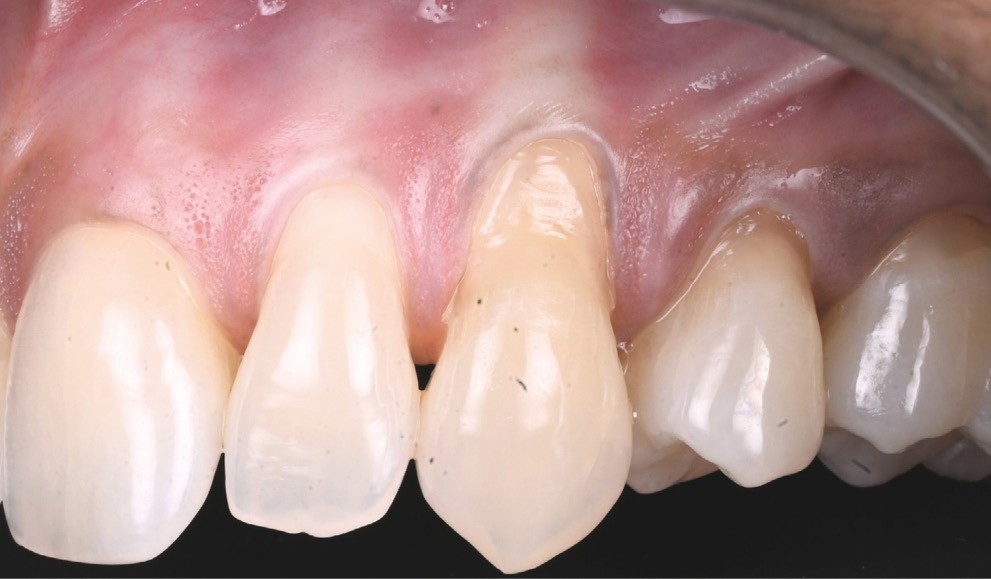

Une chirurgie combinée est réalisée (fig. 4) :

- tunnélisation secteur 1, élévation d’un lambeau secteur 2 ;

- prélèvement épithélio-conjonctif unilatéral au palais, désépithélialisé et divisé en deux ;

- greffon de lamina propria inséré dans le tunnel (secteur 1) et suturé au périoste (secteur 2) ;

- jeu de sutures au fil 6.0 : « double cross » en fils non résorbables secteur 1 / « suspendues » en fils résorbables secteur 2.